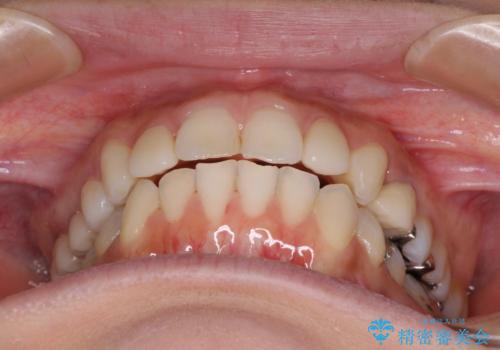

- 前歯のデコボコと矮小歯、更には痛みを感じる奥歯のむし歯を気にして来院された患者様です。

奥歯には根管治療が必要な歯があり、上顎側切歯は左右ともに矮小歯でした。

上下前歯のデコボコはワイヤーでもインビザラインでも対応可能でしたが、補綴治療が多く必要となることから、インビザラインでの矯正治療を行いながら、並行して補綴治療を行うこととしました。

まずは根管治療を行った上で矯正治療用の仮歯を装着し、矯正治療後半に補綴治療を並行して行うこととしました。